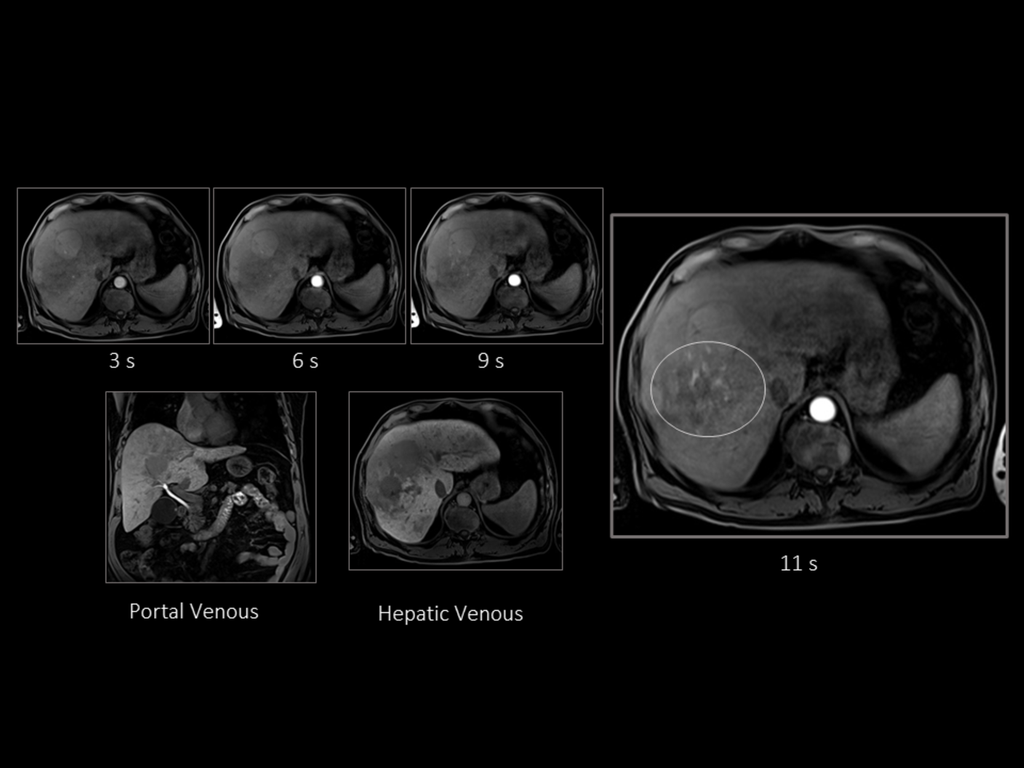

From phys.org

Treating liver cancer with microrobots piloted by a field Is Liver Cancer Always Terminal 5 year survival for liver cancer is generally higher in younger people compared to older people. To determine the stage of a case of liver cancer, your doctor. Secondary, or metastatic, liver cancers are tumors that start in another part of the body, such as the colon, then spread. Both cancer types have common causes, risk factors,. At every stage,. Is Liver Cancer Always Terminal.